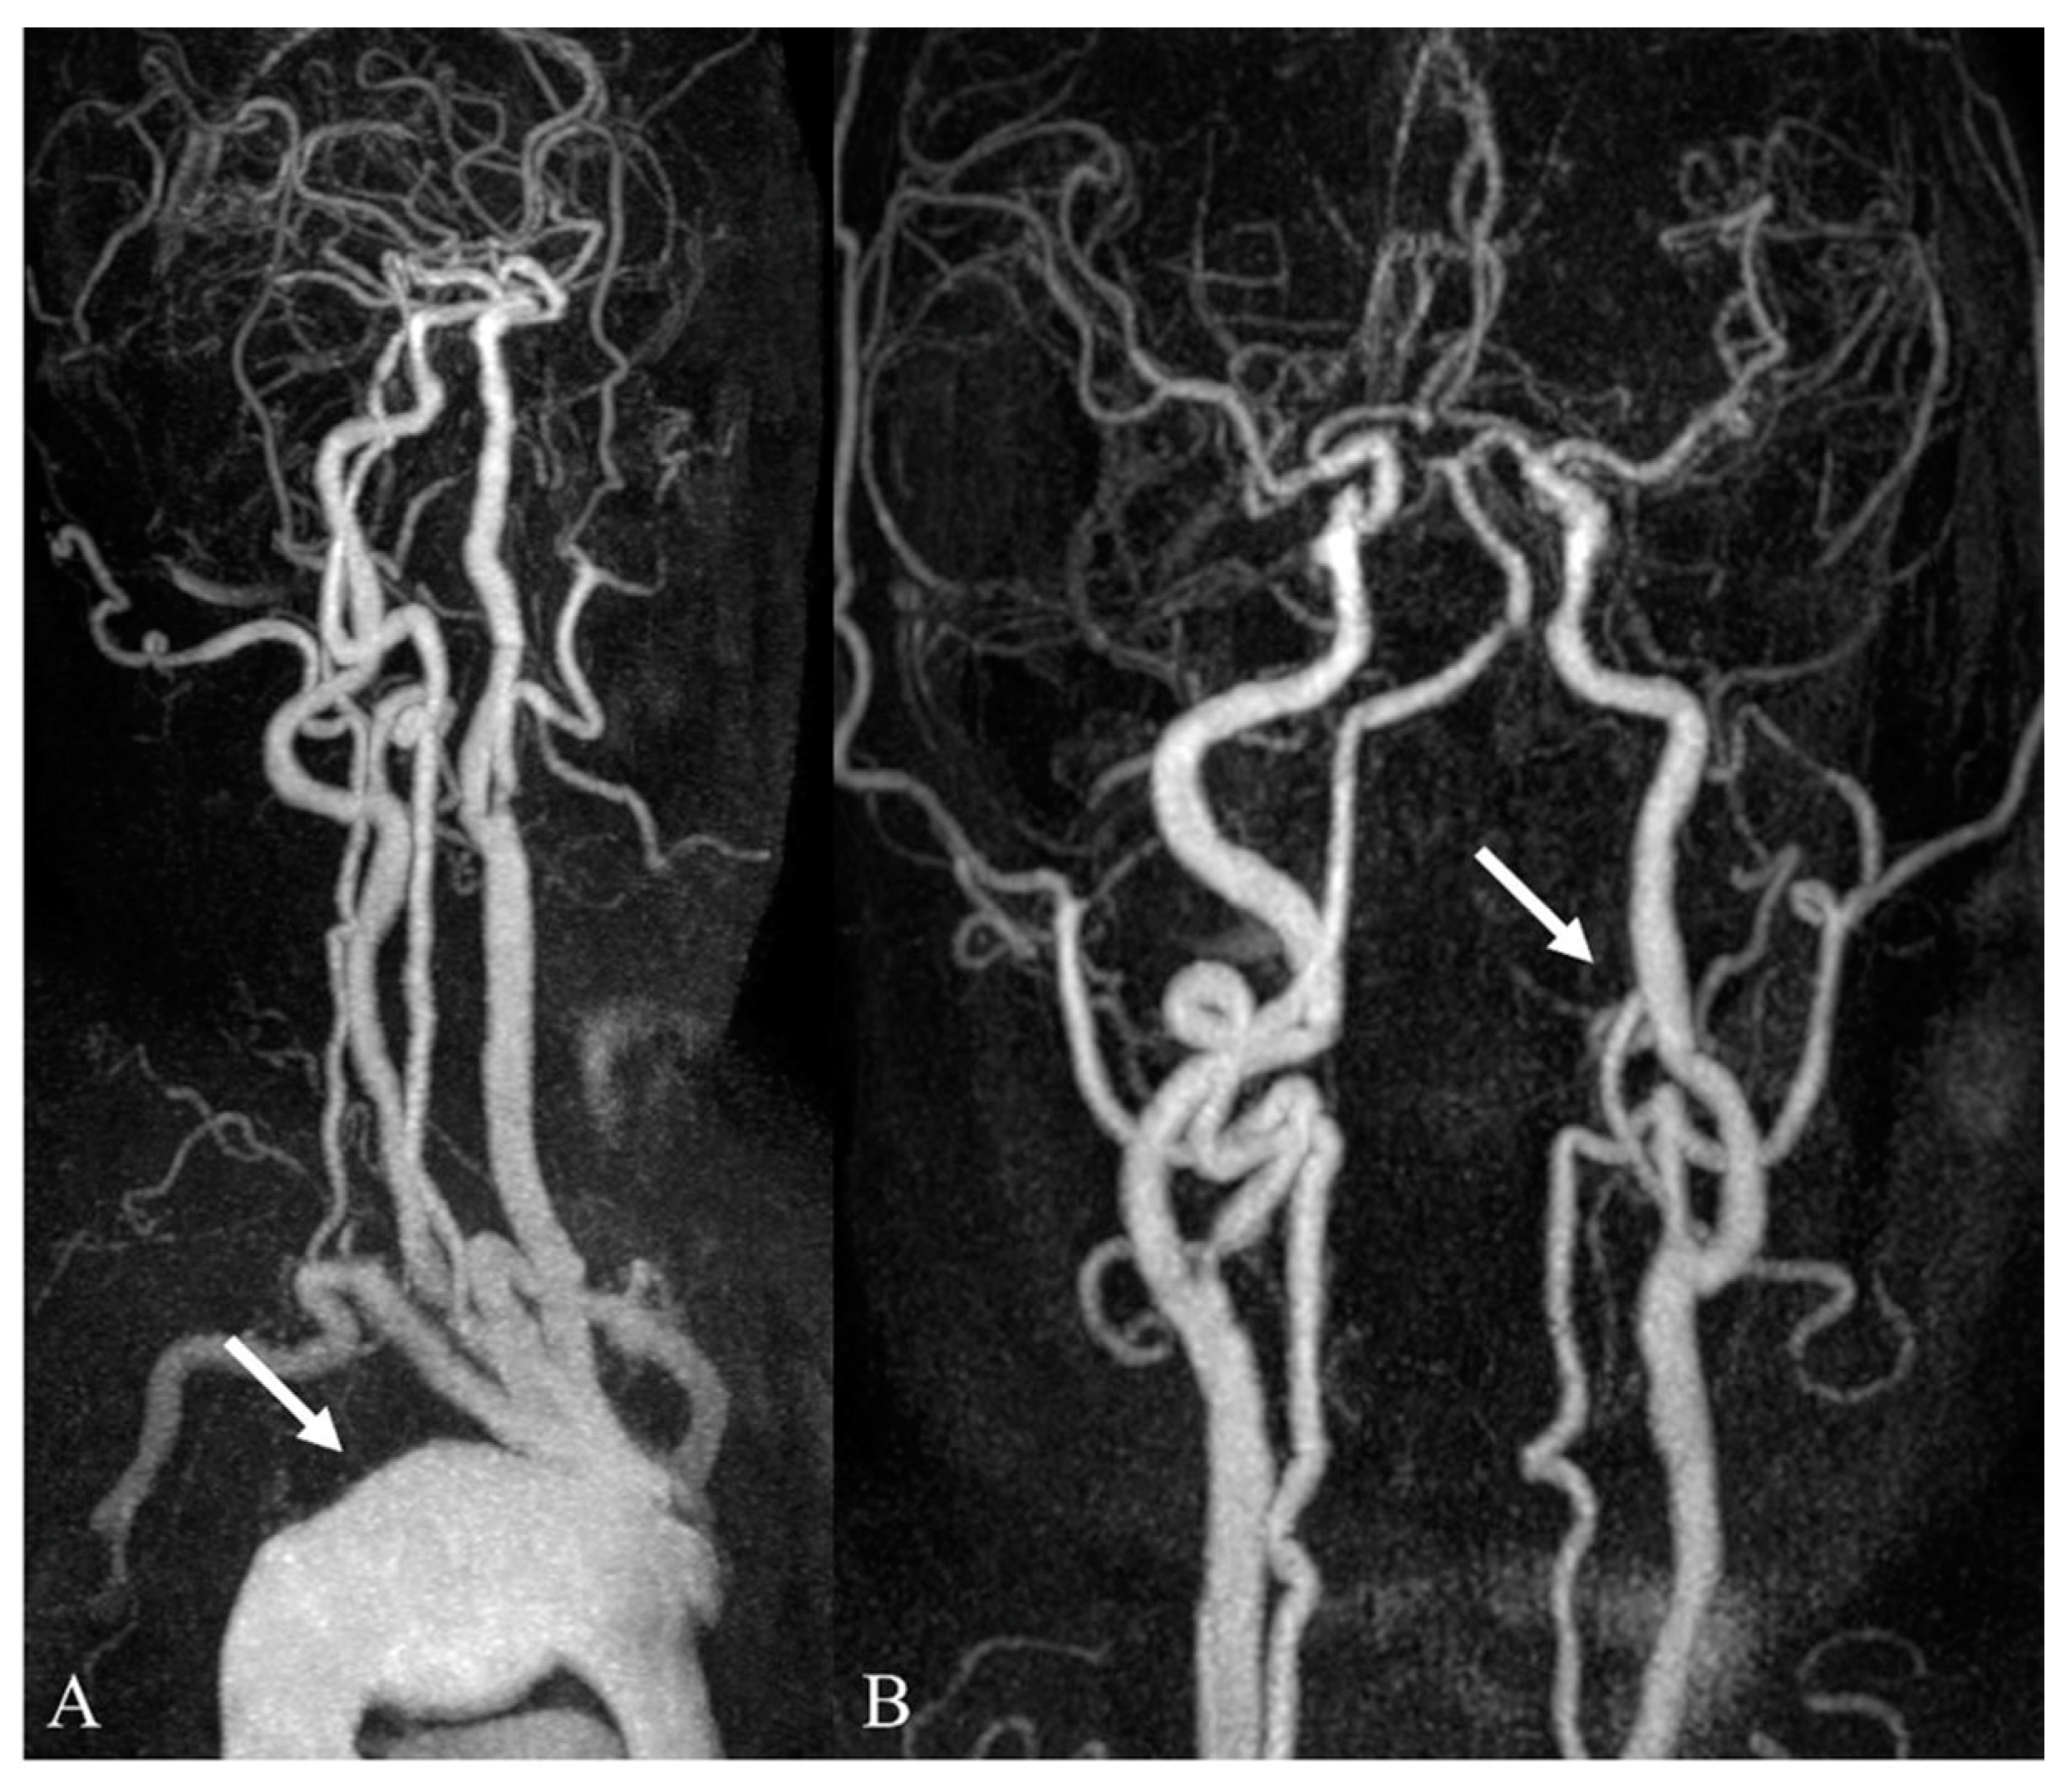

3.2. Incidental Aortic Arch Abnormalities on Contrast-Enhanced Neck MR Angiography

| Category I (Clinically significant findings) | 29/348 (8.3%) | 29/348 (8.3%) |

| Aortic dissection | 22/348 (6.3%) | |

| Aortic aneurysm | 7/348 (2.0%) | |